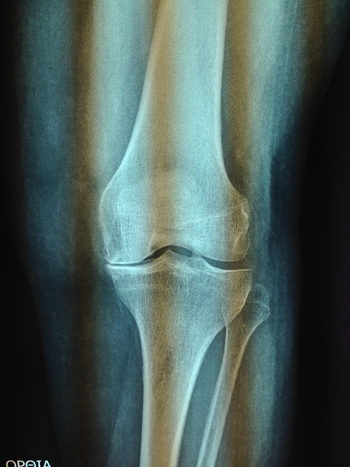

| Οστεοαρθρίτιδα γόνατος (προεγχειριτική) | Οστεοαρθρίτιδα γόνατος (μετεγχειριτική) |